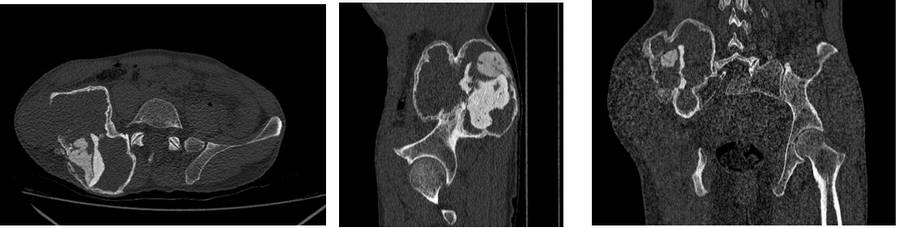

Ameliyat Öncesi: Tomografide sağ ilaik kanatda genişleme düzensizlik harabiyet ve sement varlığı görülmekte